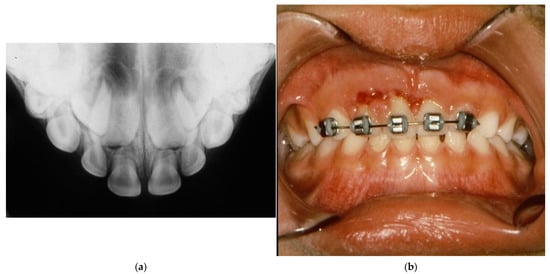

- Di Giorgio, G.; Zumbo, G.; Saccucci, M.; Luzzi, V.; Ierardo, G.; Biagi, R.; Bossù, M. Root Fracture and Extrusive Luxation in Primary Teeth and Their Management: A Case Report. Dent. J. 2021, 9, 107. [Google Scholar] [CrossRef] [PubMed]